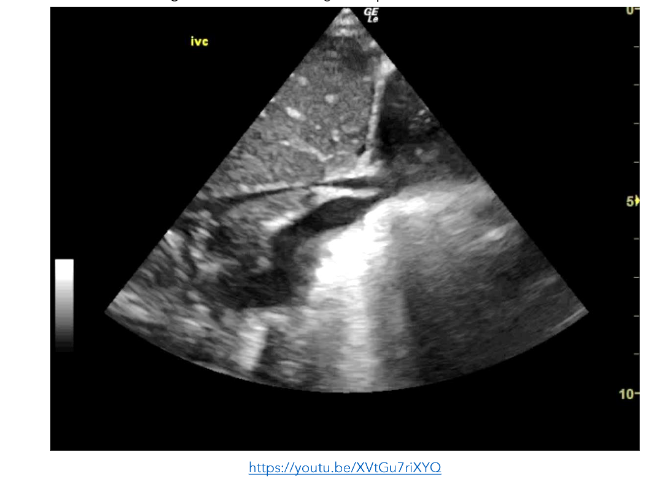

Figure 8: SC view showing small echogenic masses in the left ventricle, right ventricle and right atrium consistent with septic emboli. The right atrium is poorly visualised and cannot be assessed https://youtu.be/awqHN68tV2g